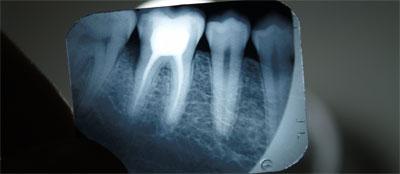

Процедуру удаления зуба назначает и проводит врач, который называется стоматолог-хирург. Перед проведением всех манипуляций хирург просматривает рентгеновские снимки челюсти больного, объясняет ему сложности проведения процедуры, информирует о противопоказаниях и последствиях.

- сделать рентгеновские снимки зуба и показать их своему стоматологу-хирургу;

Такой вид экстракции применяется во время ортодонтического лечения (исправление прикуса, постановка коронок). Решение о необходимости удаления здоровых коренных зубов принимает специалист после нескольких консультаций и рентгеновских снимков. Удаление может производиться с использованием как щипцов, так и скальпеля.